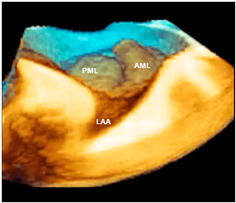

| Barlow’s disease | Barlow’s disease is the result of an abnormal accumulation of myxomatous substances (mainly proteoglycans) in the spongiosa layer, and a simultaneous disruption of collagen fibers in the fibrosa layer. As a consequence, the three-layered arrangement of the leaflets is lost. The characteristic macroscopic appearance, either in pathological specimens or in the operating room, is that of a thick, bulky, redundant leaflet, elongated chordae tendineae, and annular dilatation. The excess leaflet tissue leads to the displacement of both leaflets beyond the annulus, with a lack of coaptation and consequent MR. The figure shows an example of Barlow’s disease seen from a tangential view largely protruding into the left atrium. LAA = left atrial appendage, AML = anterior mitral leaflet; PML = posterior mitral leaflet. |  |